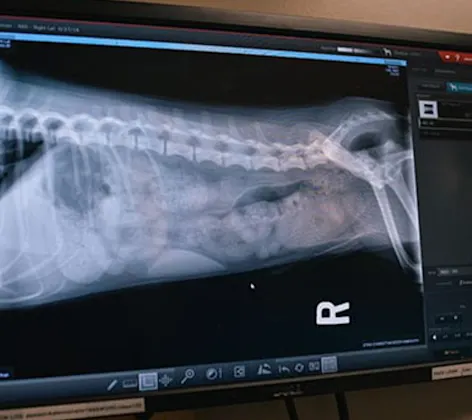

Diagnostic Imaging

Diagnostic imaging technology has dramatically improved the speed and accuracy with which we can diagnose and treat serious diseases affecting pets.